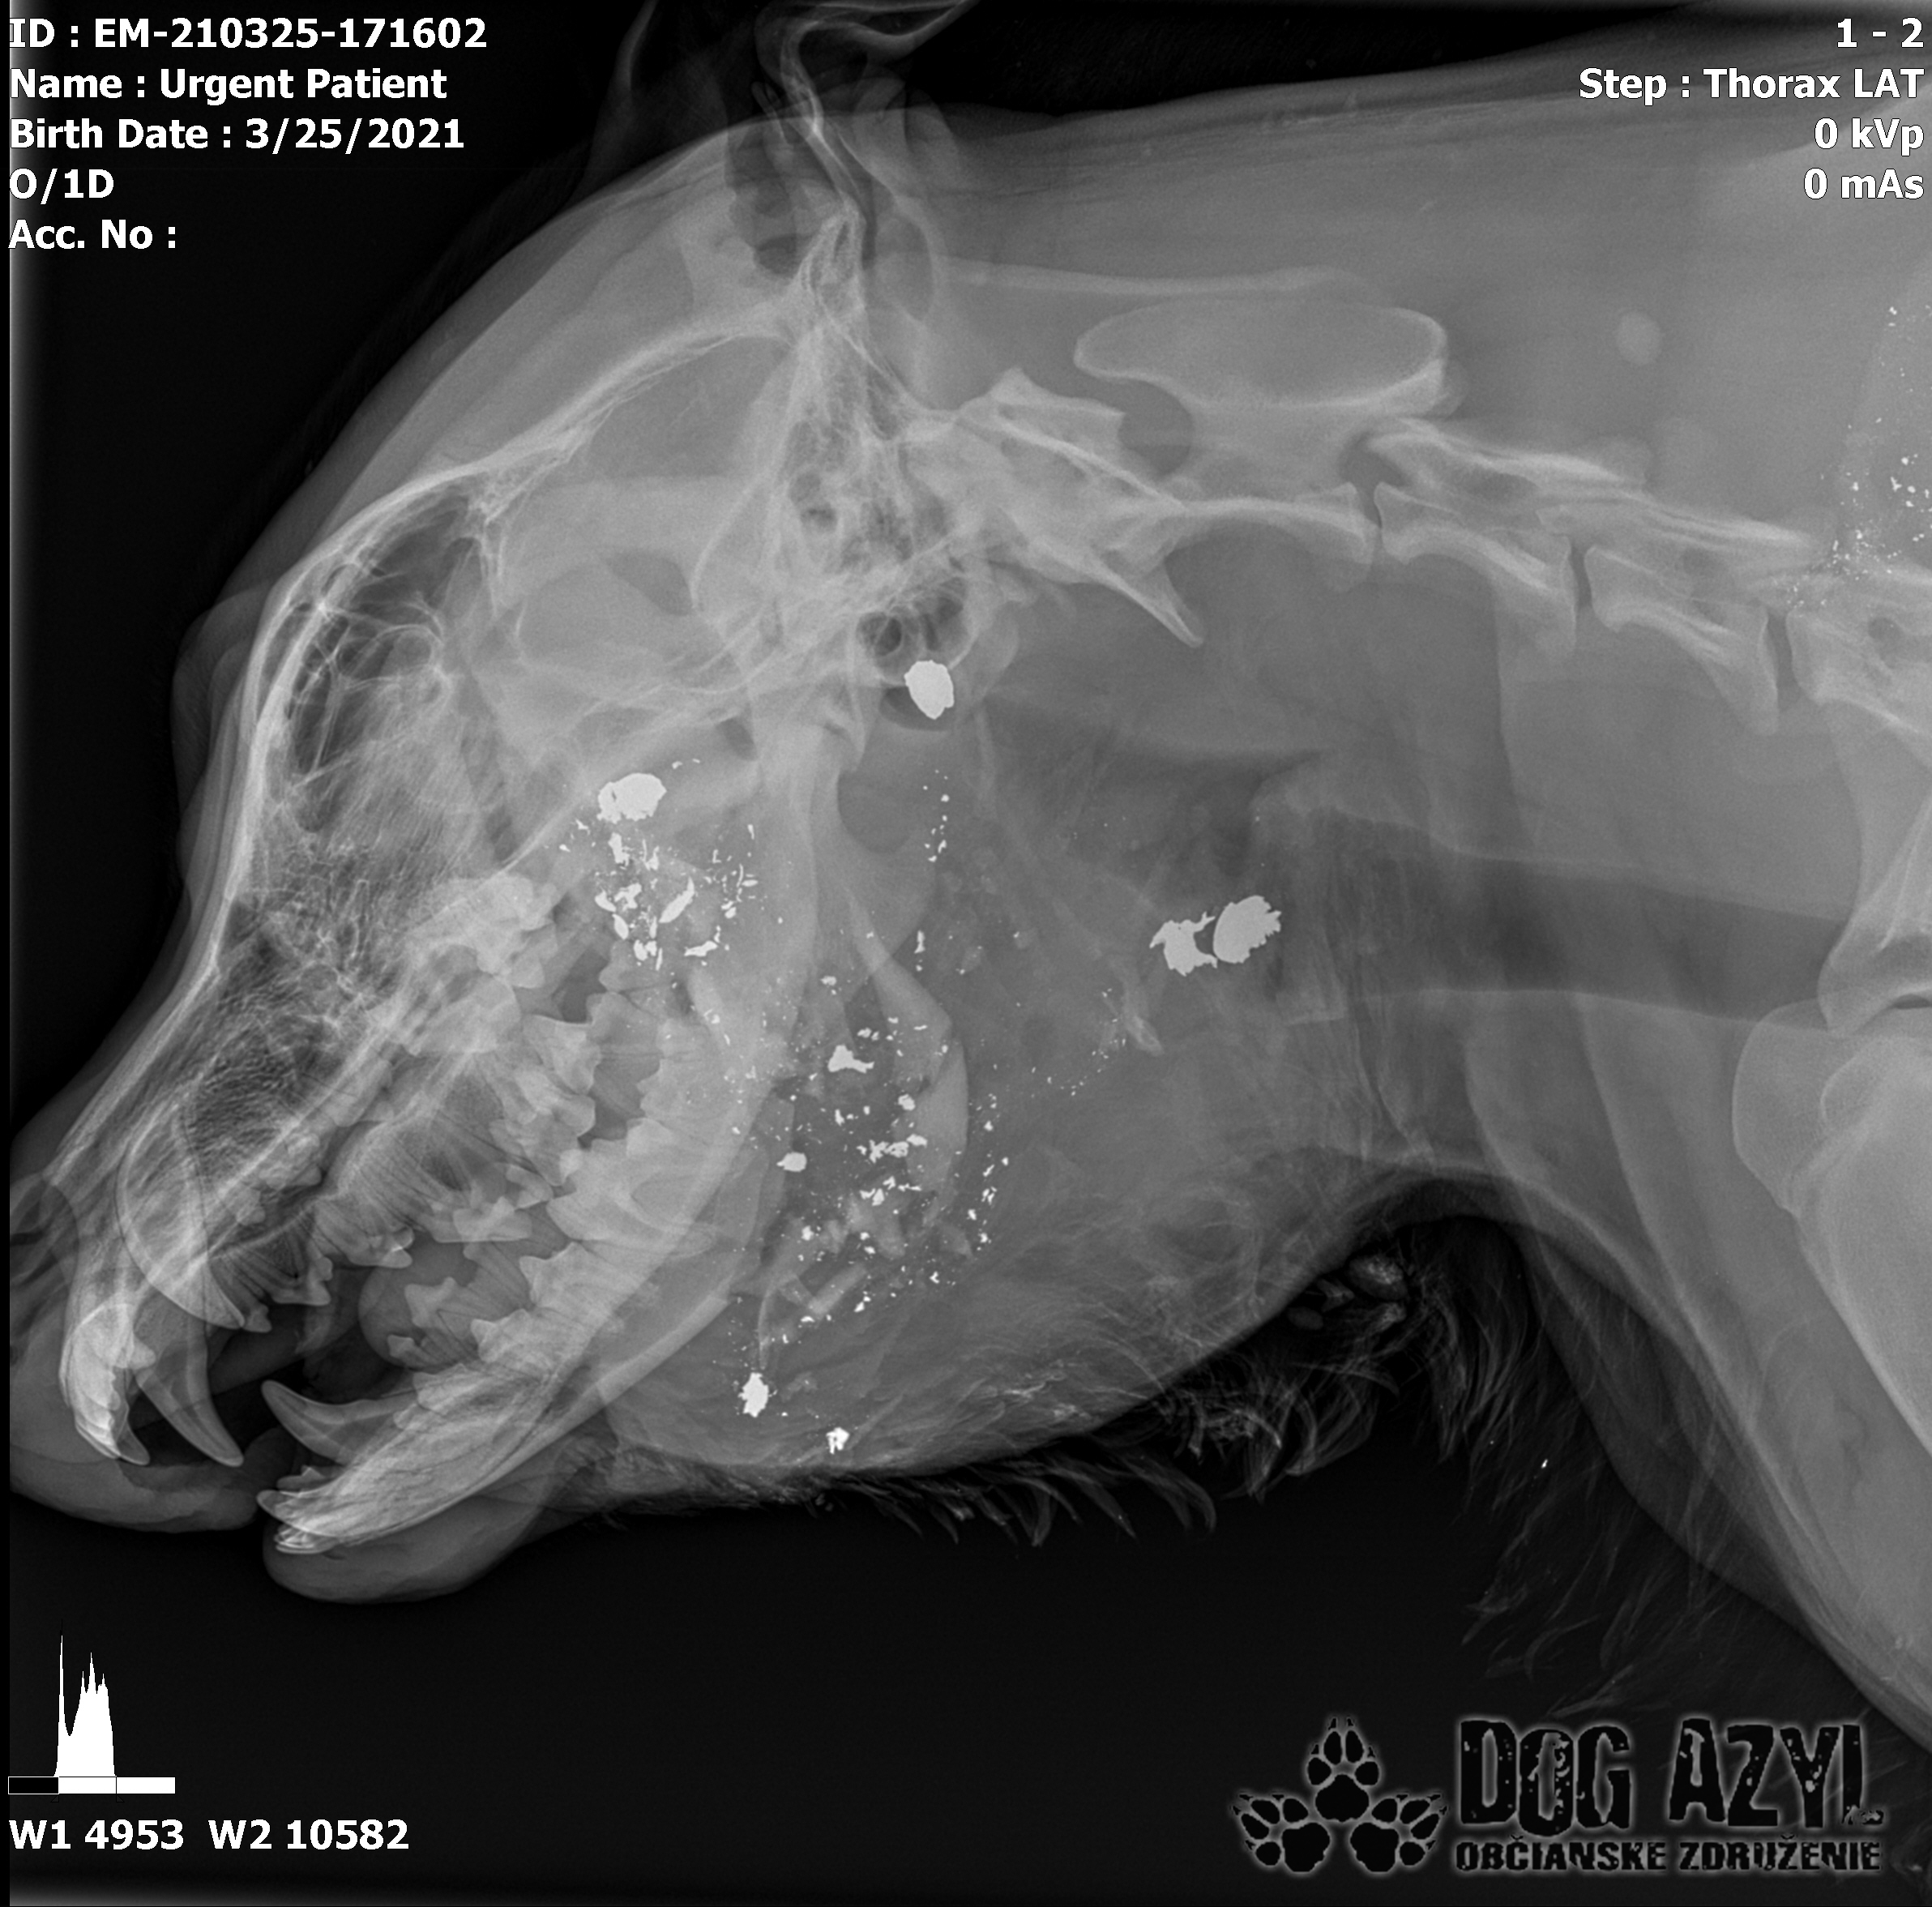

/Strašne to chcem dopísať tak, aby to bolo čitateľné a pochopiteľné, ale celá sa klepem od zlosti a nevidím cez slzy.../ Lebo Ona už meno nikdy nebude mať.. On dostal meno Baris a bojuje o život!!! Má dolámanú sánku a je v šoku!!! Dostal prvú pomoc, analgetiká a priorita bola znížiť jeho teplotu z 41,4°C!!!

Ústami nevie pohnúť, jazyk si nevie ovládať a tak sa sám nedokáže schladiť ani napiť. Podľa RTG sú srdiečko a pľúca v poriadku, ale vôbec nemá vyhraté!!! Niekto chcel Barisa zlikvidovať, ale my za neho budeme bojovať do posledného dychu!!! Zajtra bude prevezený na veterinárnu kliniku Sibra centrum, kde ho čaká team špecialistov z oblasti chirurgie, neurológie a ortopédie. Ak je čo i len najmenšia nádej, že Baris bude môcť žiť, tak BARIS BUDE ŽIŤ!!!